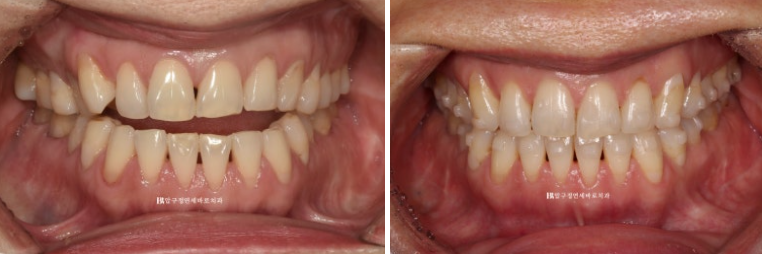

23.05~23.12

앞니가 떠 있는 개방교합에서

첫번째 작은어금니까지 8개 치아는 떠있고 두번째 작은어금니부터 큰어금니까지 3개씩 닿아있는 상태입니다.

이런 상태에서는 닿고있는 위 어금니 3개씩 총 6개 치아를 함입시키는 치료계획으로 진행합니다.